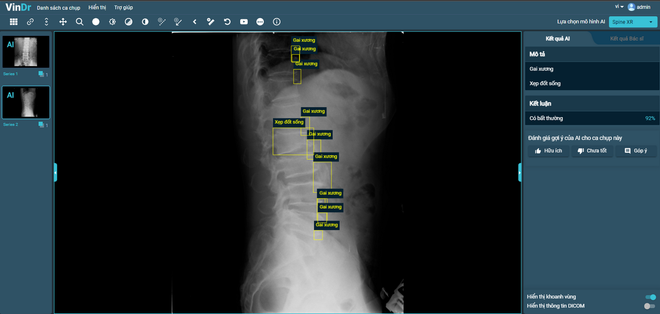

Sau hơn 1 năm tiếp tục nghiên cứu và phát triển, VinBigdata đã tiếp tục phát triển thành công tính năng chẩn đoán X-quang cột sống, phát hiện 6 loại tổn thương phổ biến tại Việt Nam, bao gồm: gai xương; hẹp khe đĩa đệm; vật liệu phẫu thuật; hẹp lỗ tiếp hợp; trượt đốt sống và xẹp đốt sống với độ chính xác khoảng 90%.

Vingroup: Ứng dụng AI-VinDr để giải bài toán y tế bền vững ảnh 1VinDr hoàn thiện tính năng mới SpineXR, hỗ trợ chẩn đoán ảnh X-quang cột sống với độ chính xác khoảng 90%. (Nguồn: Vingroup)